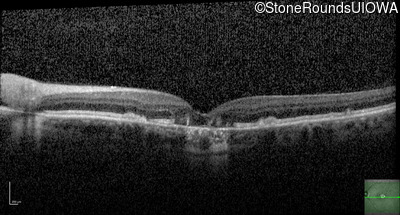

Optical Coherence Tomography - Right - 20/20

Exemplar / OCT Stack

Optical Coherence Tomography - Left - 20/40 +1